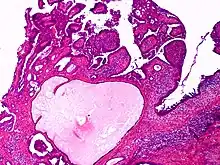

| Apocrine gland carcinoma, papillary type | |